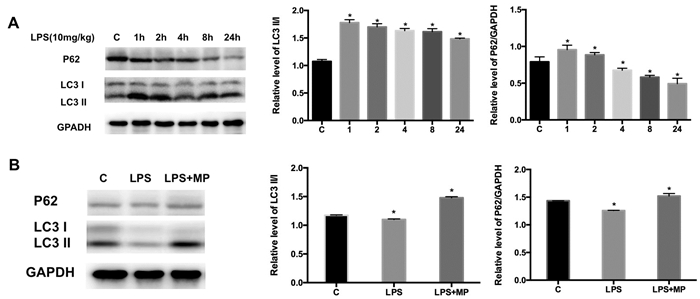

与健康对照组比较,LPS条件下(2 h内)肝细胞自噬标志蛋白LC3 Ⅱ/Ⅰ表达上调自噬水平呈现短暂升高,2 h后呈现降低趋势,24 h时自噬标志蛋白LC3 Ⅱ/Ⅰ水平明显降低;LPS处理24h时,P62表达水平明显降低(图 5 A、B)。与LPS组小鼠相比,LPS+MP组小鼠肝组织内LC3 Ⅱ/Ⅰ、P62表达明显上调(图 5 B)。

| 图A对照组(C), LPS(10 mg/kg)腹腔注射1、2、4、8、24 h,肝组织中自噬蛋白P62和Ⅱ/Ⅰ的表达变化;图B LPS处理48 h,MP干预48 h时,肝组织自噬蛋白P62和LC3 Ⅱ/Ⅰ的表达变化 图 5 肝组织自噬蛋白LC3 Ⅱ/Ⅰ、P62变化 Figure 5 The expressionof autophagosomal protein LC3 Ⅱ/Ⅰ and P62 in liver |

本研究结果证实MP能有效改善LPS诱导的小鼠肝损伤,表现为血清ALT、TBIL、TBA水平显著改善,炎症因子TNF-α、IL-6、IL-1β表达水平显著降低;进一步研究发现,MP能增加自噬标志蛋白LC3 Ⅱ/Ⅰ表达,提示MP可能通过激活肝细胞自噬发挥肝保护作用,改善LPS诱导的肝损伤程度。

肝损伤的自我保护机制具有时间依赖性。LPS处理6 h内肝脏自我保护能力增强,24 h后呈减弱趋势[21-23]。自噬激活在脓毒症导致的多器官功能衰竭中起自我保护作用,包括肝脏、肾脏、肺脏、心脏等[24-29]。Chen等[22]研究发现脓毒症早期肝细胞内自噬激活,而后期自噬减弱可能是肝衰竭发生的重要因素。P62与LC3 Ⅰ/Ⅱ是重要的自噬调节蛋白,P62通过LIR区域(LC3-interacting region)与Atg8/LC3结合来调节自噬[30]。LPS处理小鼠促进肝细胞内LC3 Ⅰ向LC3 Ⅱ转变以及P62蛋白的积累[23]。本研究发现:LPS诱导自噬激活作用在2h内到高峰,之后逐渐减弱;提示LPS刺激条件下,早期自噬激活可能是肝细胞的自我保护反应;而后自噬处于抑制状态,可能是肝损伤恶化的关键因素之一。MP干预后肝脏的自噬活性显著被激活,自噬蛋白LC3 Ⅱ和P62的表达明显增加,提示MP能有效激活LPS处理后期对肝细胞自噬的抑制作用进而发挥肝保护作用。Xue等[31]研究发现糖皮质激素激活自噬依赖于哺乳动物雷帕霉素靶蛋白(mammalian target of rapamycin, mTOR)途径;而本研究中MP激活自噬发挥肝保护是否与mTOR途径有关,尚需深入研究。此外,Shi等[32]研究发现激活自噬能抑制IL-1β表达,抑制NALP3炎性体,进而调节IL-18和IL-1β的表达[33];依赖P62蛋白的选择性自噬可清除受损线粒体,终止炎性体活化及降低TNF-α、IL-18和IL-1β的表达[34];提示自噬可能通过调控炎症反应发挥保护作用。本研究中,LPS+MP组自噬蛋白P62较LPS组增加,小鼠肝脏TNF-α、IL-1β、IL-6等炎症因子的表达水平显著低于单纯LPS组,提示MP能有效降低LPS导致的高炎症因子水平,可能和自噬激活相关。